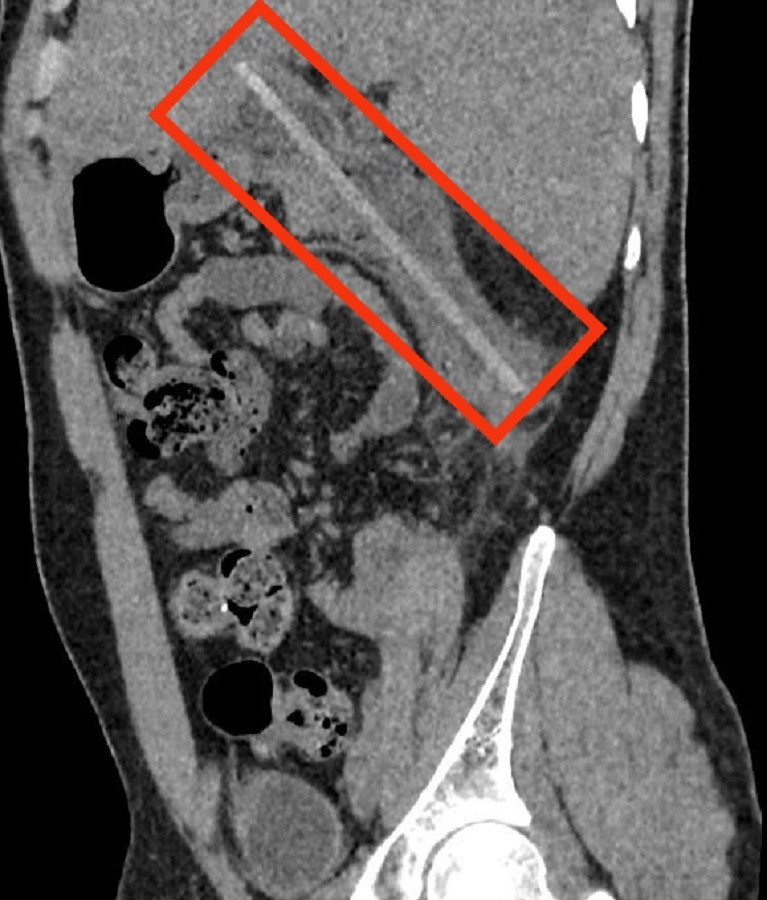

| Hình ảnh CT cho thấy dị vật nằm trong cơ thể của bệnh nhân |

Khoảng 3 ngày trước khi nhập viện, bệnh nhân có biểu hiện đau bụng âm ỉ vùng quanh rốn, cơn đau ngày càng dồn dập và nghiêm trọng phải nhập viện cấp cứu. Ngay khi tiếp nhận, các bác sĩ đã chụp CT và phát hiện có một dị vật giống như que gỗ tại tá tràng của người bệnh.